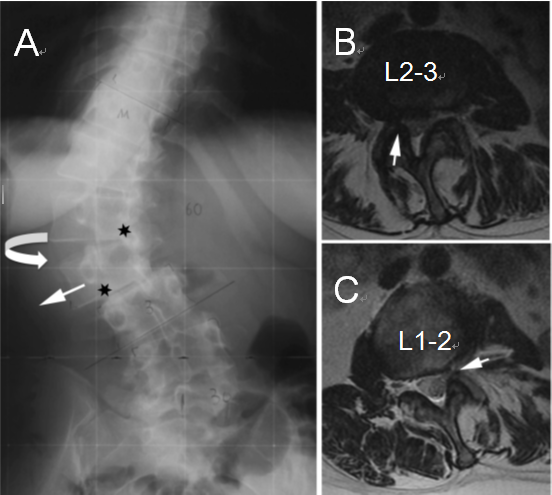

(A)腰椎X线片显示椎体在L1-L2处旋转,椎间盘向凹侧突出,在L2-L3处出现侧向半脱位,椎间盘向凸侧突出;星号表示狭窄部位

(B)轴向MRI显示L2–L3处的凸侧椎间孔狭窄,形成开放性半脱位

(C)L1–L2处的凹侧椎间孔狭窄,形成闭合性半脱位。